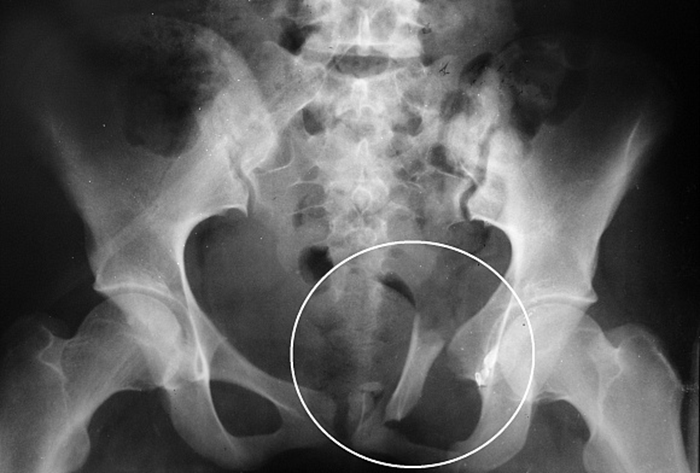

Что показывают снимки крестцово-копчикового отдела

Профессиональный рентгенолог на них может рассмотреть все костные структуры крестцово-копчикового отдела и изменения в них. Это позволяет диагностировать:

- Остеомиелит.

- Вывих и перелом позвонков.

- Надрыв и разрыв межпозвоночных хрящей.

- Наличие у копчика отрыва от основного сочленения.

- Появившиеся первичные новообразования.

- Патологические изменения, свидетельствующие об остеохондрозе и аномалиях в костных структурах.

По полученным снимкам рентгенолог проверяет состояние тел позвонков копчика, расположение в нем костных структур и множество других параметров. Результаты вносятся в заключение, по результатам которого лечащий врач ставит тот или иной диагноз.